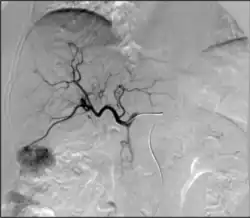

Selective internal radiation therapy (also known as SIRT or Y-90 radioembolization): Injection of small beads loaded with a radioactive isotope, yittrium-90 (Y-90), into blood vessels feeding a tumor to deliver a lethal dose of radiation to cause cell death.[67] Can be performed in a segmental (radiation segmentectomy) or a lobar (radiation lobectomy) fashion. Radiation lobectomy is commonly performed with the goal of inducing growth of the non-diseased lobe in order to have adequate liver function necessary to undergo surgical resection.

Portal vein embolization (PVE): delivery of embolic material into the portal vein feeding the lobe of liver containing the tumor(s) of interest to induce growth of the non-diseased lobe to maintain adequate liver function necessary to undergo surgical resection of lobe containing the tumor(s).[68]